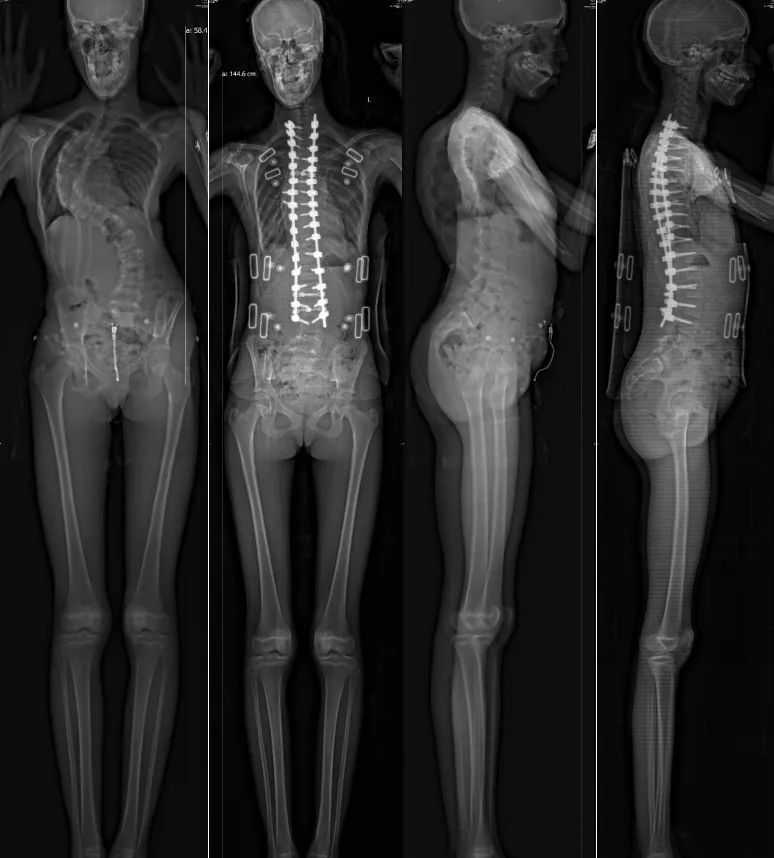

2025年7月,杨军林教授团队历经4小时高难度手术,成功实施截骨松解及去旋转技术,巧妙保留患者20%弯腰功能。术后脊柱畸形矫形率接近80%,患者“长高”8厘米,一周左右即可正常行走活动,可以自如地弯腰、后仰以及上下台阶。

△患者的术前术后影像学对比